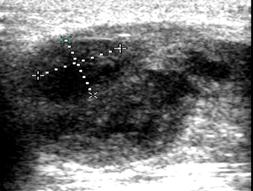

При гнойном воспалении происходит дальнейшее исчезновение дифференциации слоев лимфоузла. Форма становится шарообразной, истончается капсула. В структуре появляются анэхогенные участки, соответствующие очагам деструкции, которые в дальнейшее сливаются. Картина гнойного лимфаденита представлена на рис. 5.

А Б

Рис. 5. Гнойный лимфаденит (обозначен маркерами)

Представляется интересным динамическое эхографическое исследование. Ниже представлена эхографическая картина острого гнойного лимфаденита у девочки Г. трёх лет. На рис. 6 (А) представлена картина острого гнойного лимфаденита в день поступления.

Эхограмма этой же больной через три дня после вскрытия и дренирования гнойника (рис. 6.Б), обращает уменьшение размеров участка гнойного расплавления, отсутствие гнойного затека. Что говорит об эффективности лечения. На следующем рисунке (рис. 7), представлена эхограмма этой же пациентки, выполненная на 11 сутки, с практически восстановленной структурой лимфоузла.

Таким образом, благодаря эхографическому исследованию можно выявить стадию гнойного расплавления, точно локализовать процесс, проследить динамику и предупредить возможные осложнения. Также метод позволяет проследить результат лечения после хирургического вмешательства.

Рис. 6. Эхограмма острого гнойного лимфаденита

(маркерами и стрелкой обозначена зона гнойного расплавления)